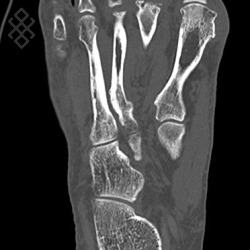

Scanner du Pied